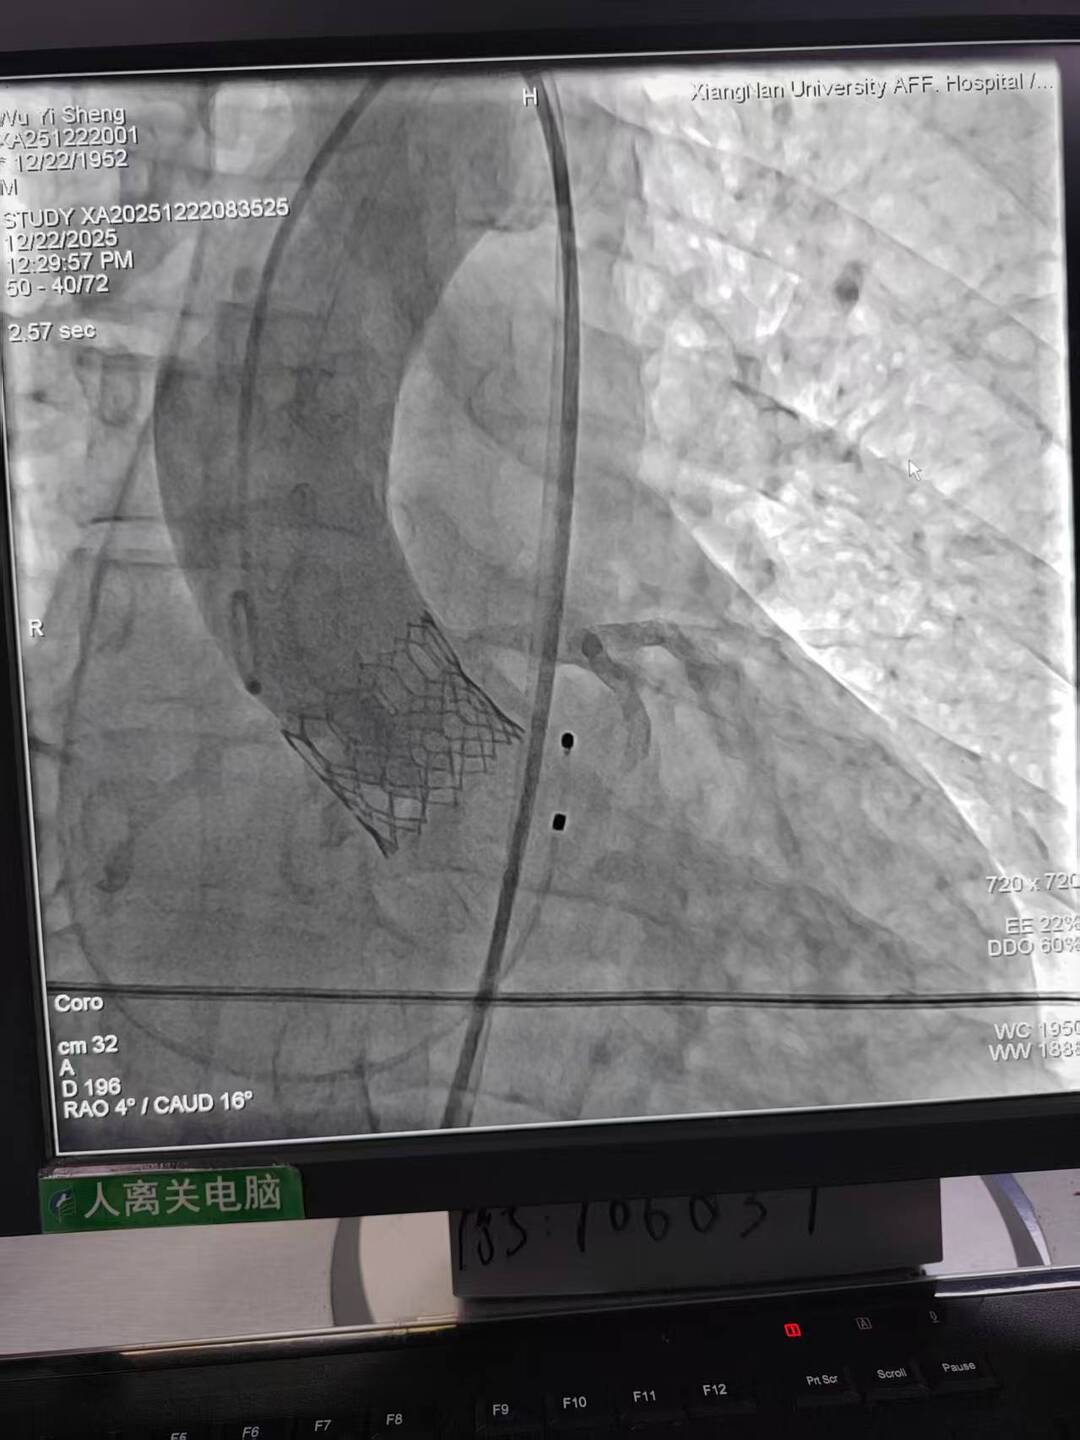

手术过程犹如在心脏内进行的“微雕”和“换门”工程,步骤环环相扣,每一步都考验着术者的技术功底与团队协作默契。术中,团队首先利用先进的可扩张血管鞘,在严重钙化狭窄的右侧股动脉腔内成功建立安全的手术通路;随后经该微创入路,先通过球囊扩张术为冠状动脉植入支架,快速恢复心肌血供;紧接着,在同一手术台、同一入路下,精准将人工主动脉瓣输送至病变位置并成功释放,顺利替换失灵的原生瓣膜。整个过程中,团队成功克服了外周血管入路困难的核心挑战,确保手术各环节无缝衔接、精准落地。

术后,患者主动脉瓣功能即刻恢复正常,冠状动脉血流重回通畅,胸闷、气促等不适症状显著缓解。经过后续康复护理,患者已顺利出院,重获正常生活能力。